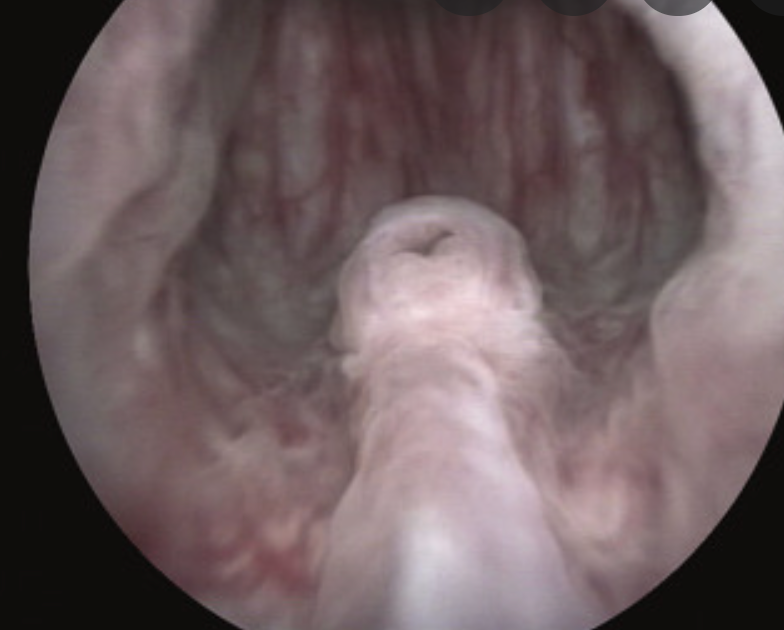

What is this proceedure?

What is the indication?

What complication is seen here?

Cystostomy

Indication

• Bladder outlet obstruction

Abstract :

Patients with long-term suprapubic cystostomy can rarely develop squamous cell carcinoma (SCC) of the suprapubic cystostomy tract. In addition to the few reported cases in the literature, this paper reports a case of suprapubic cystostomy SCC in an 88-year-old man without bladder involvement. Vigilance about any abnormal lesion at the site of suprapubic cystostomy is important among health providers and patients for early detection of SCC.